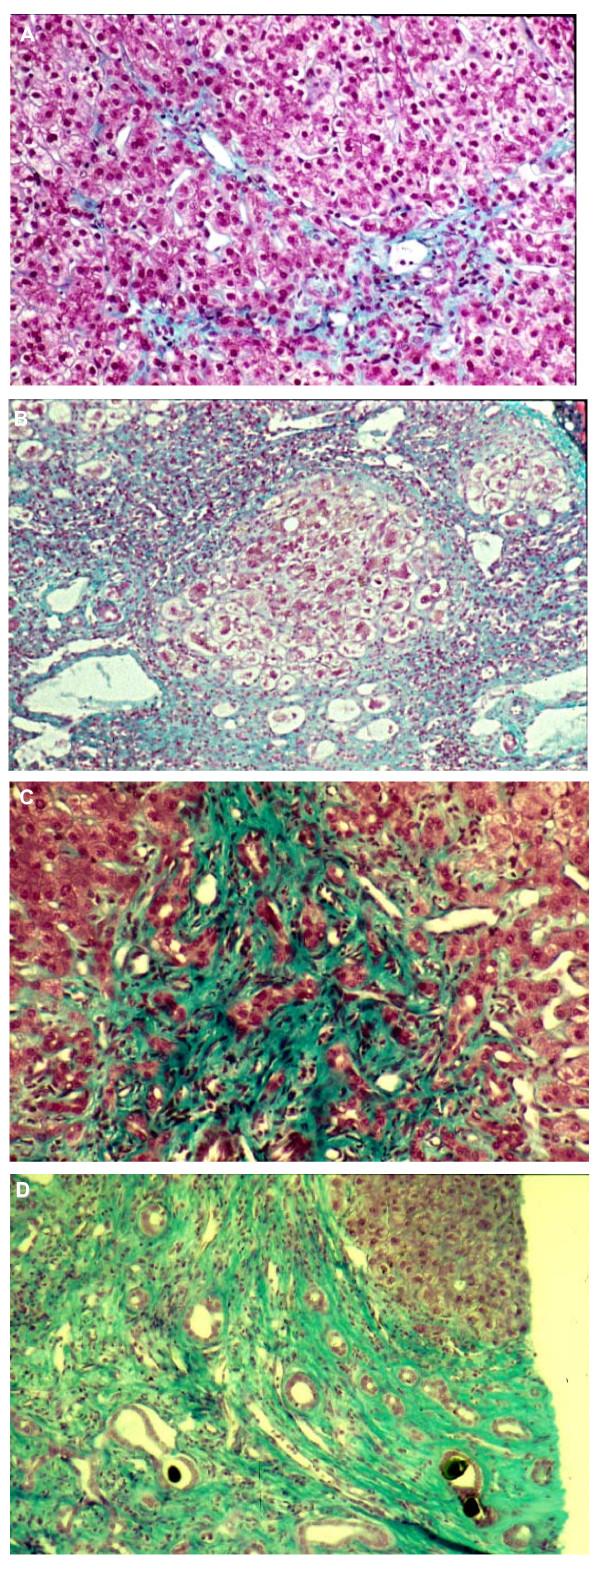

Progressive familial intrahepatic cholestasis (PFIC) refers to heterogeneous group of autosomal recessive disorders of childhood that disrupt bile formation and present with cholestasis of hepatocellular origin. The exact prevalence remains unknown, but the estimated incidence varies between 1/50,000 and 1/100,000 births. Three types of PFIC have been identified and related to mutations in hepatocellular transport system genes involved in bile formation. PFIC1 and PFIC2 usually appear in the first months of life, whereas onset of PFIC3 may also occur later in infancy, in childhood or even during young adulthood. Main clinical manifestations include cholestasis, pruritus and jaundice. PFIC patients usually develop fibrosis and end-stage liver disease before adulthood. Serum gamma-glutamyltransferase (GGT) activity is normal in PFIC1 and PFIC2 patients, but is elevated in PFIC3 patients. Both PFIC1 and PFIC2 are caused by impaired bile salt secretion due respectively to defects in ATP8B1 encoding the FIC1 protein, and in ABCB11 encoding the bile salt export pump protein (BSEP). Defects in ABCB4, encoding the multi-drug resistant 3 protein (MDR3), impair biliary phospholipid secretion resulting in PFIC3. Diagnosis is based on clinical manifestations, liver ultrasonography, cholangiography and liver histology, as well as on specific tests for excluding other causes of childhood cholestasis. MDR3 and BSEP liver immunostaining, and analysis of biliary lipid composition should help to select PFIC candidates in whom genotyping could be proposed to confirm the diagnosis. Antenatal diagnosis can be proposed for affected families in which a mutation has been identified. Ursodeoxycholic acid (UDCA) therapy should be initiated in all patients to prevent liver damage. In some PFIC1 or PFIC2 patients, biliary diversion can also relieve pruritus and slow disease progression. However, most PFIC patients are ultimately candidates for liver transplantation. Monitoring of hepatocellular carcinoma, especially in PFIC2 patients, should be offered from the first year of life. Hepatocyte transplantation, gene therapy or specific targeted pharmacotherapy may represent alternative treatments in the future.

进行性家族性肝内胆汁淤积症(PFIC)是一组异质性常染色体隐性遗传性儿童疾病,会破坏胆汁形成,并表现为肝细胞源性胆汁淤积。确切的患病率尚不清楚,但估计发病率在每50000至100000例出生中出现1例。已确定三种类型的PFIC,它们与参与胆汁形成的肝细胞转运系统基因突变有关。PFIC1和PFIC2通常在出生后的头几个月出现,而PFIC3也可能在婴儿期后期、儿童期甚至青年期发病。主要临床表现包括胆汁淤积、瘙痒和黄疸。PFIC患者通常在成年前发展为肝纤维化和终末期肝病。PFIC1和PFIC2患者的血清γ-谷氨酰转移酶(GGT)活性正常,但PFIC3患者的GGT活性升高。PFIC1和PFIC2均分别由编码FIC1蛋白的ATP8B1缺陷以及编码胆盐输出泵蛋白(BSEP)的ABCB11缺陷导致胆盐分泌受损引起。编码多药耐药3蛋白(MDR3)的ABCB4缺陷会损害胆汁磷脂分泌,从而导致PFIC3。诊断基于临床表现、肝脏超声、胆管造影和肝脏组织学,以及用于排除儿童胆汁淤积其他病因的特定检查。MDR3和BSEP肝脏免疫染色以及胆汁脂质成分分析有助于筛选出可进行基因分型以确诊的PFIC候选者。对于已鉴定出突变的受影响家庭,可进行产前诊断。所有患者均应开始使用熊去氧胆酸(UDCA)治疗以预防肝损伤。在一些PFIC1或PFIC2患者中,胆汁转流也可缓解瘙痒并减缓疾病进展。然而,大多数PFIC患者最终都需要进行肝移植。应从出生第一年起对肝细胞癌进行监测,尤其是PFIC2患者。肝细胞移植、基因治疗或特定的靶向药物治疗可能是未来的替代治疗方法。